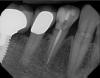

A 71-year-old man presented with acute pain in tooth No. 29 that was spontaneous, unresponsive to vitality testing, and sensitive to percussion. He was referred to an endodontist for treatment of acute apical periodontitis due to the non-vitality of the nerve. Because of the multiple restorations and lingual decay of the tooth, enamel and dentin were compromised, causing the tooth to be biomechanically at high risk and requiring an eventual post-and-core and crown (Figure 1 and Figure 2). Endodontic care included nonsurgical intracanal therapy and creating room for a post space.

Bonding the restoration requires a meticulous process to achieve success. Isolation from salivary and gingival fluids is a must. Isolation by rubber dam or a similar product is essential. Crevicular fluid must kept under control to avoid contamination. In addition, the dentin of the preparation was treated and rinsed with 2.0% chlorhexidine gluconate to remove any debris (Figure 14 and Figure 15). Selective etching of the enamel with 35% phosphoric acid for 15 seconds was followed by thorough rinsing with water. Final cementation was performed using a dual-mix translucent formulation containing primer, adhesive, and cement. The cement had an unlimited working time and 100% polymerization, and it completely light-cured in 40 seconds. Final marginal cleanup was easily performed with a carbide ET9 12-fluted bur. The patient was pleased with the convenience and esthetic results (Figure 16).

Fig 14. Microetching removes all surface debris from the preparation, enhancing bond strength.

Figure 14

Fig 15. 2.0% chlorhexidine gluconate decontaminates bacterial burden in the area of the bonding.

Figure 15